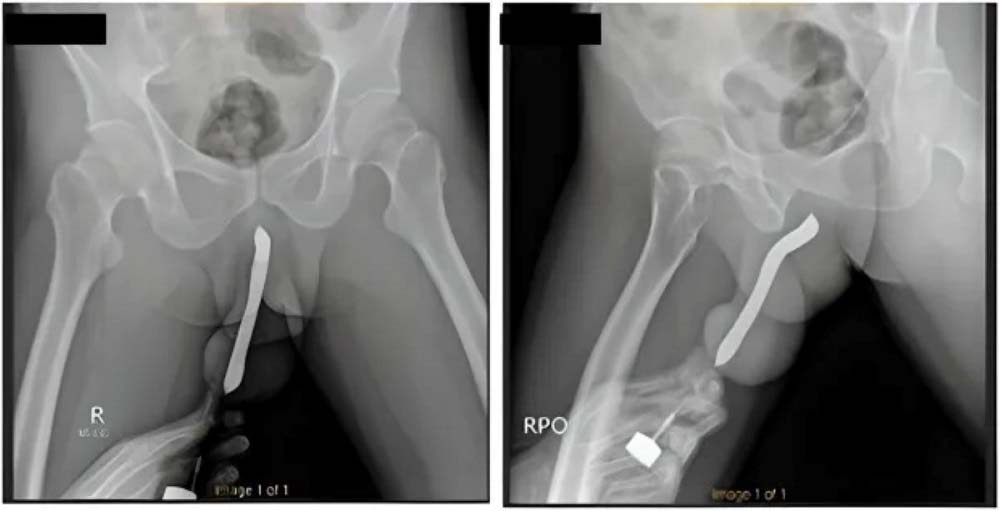

지난 1일 영국 매체 더 선은 성기에 칫솔을 삽입했다가 성관계 중 성기가 골절된 43세 인도네시아 남성 A씨의 사연을 소개했다. A씨는 "성관계 중 성기가 부러졌다"며 "성기를 재건하고 칫솔을 빼내기 위해 2시간 동안 수술받았다"고 말했다. 이어 그는 "2017년 불법 시술로 성기에 칫솔을 집어넣었다"고 밝혔다. 인도네시아 성 학자인 보이크 디안 누그라하 박사는 "사람들이 음경을 크게 만들기 위해 칫솔, 실리콘, 돌, 구슬 등을 성기에 넣지만 효과가 없을 뿐더러 위험하다"고 말했다.